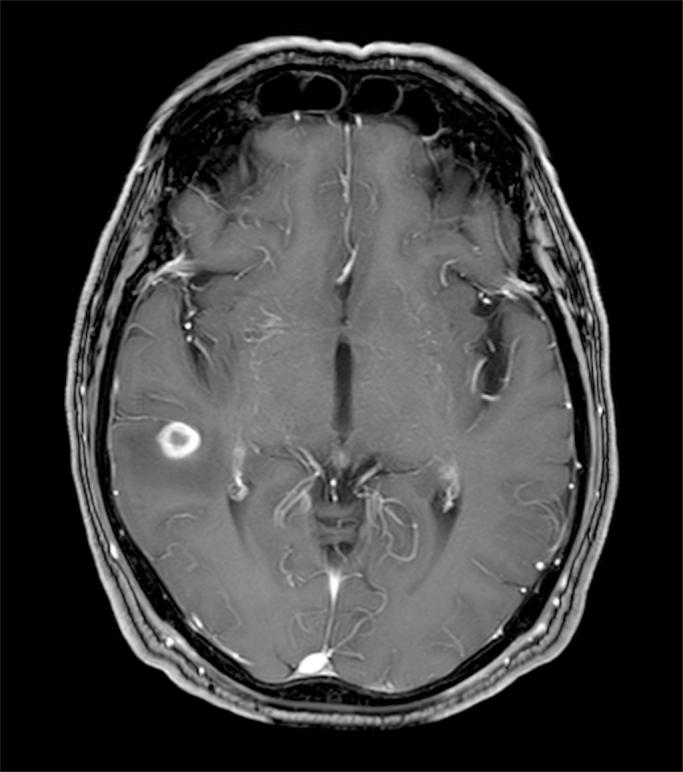

Paracoccidioidomycosis is a systemic fungal infection caused by and endemic in certain areas of Central and South America. We report a case of a 62-year-old-man with a complex history of tuberculosis and imaging findings of a cerebral lesion and bilateral adrenal enlargement. Biopsy of adrenal gland revealed . This case highlights the importance of travel history for diagnosis of paracoccidioidomycosis in non-endemic areas and emphasizes the clinical and histopathological similarities with tuberculosis.

副球孢子菌病是一种由[未提及具体病因]引起的系统性真菌感染,在中美洲和南美洲的某些地区流行。我们报告一例62岁男性病例,该患者有复杂的结核病病史,脑部病变及双侧肾上腺增大的影像学表现。肾上腺活检显示[未提及活检结果]。该病例强调了旅行史在非流行地区诊断副球孢子菌病中的重要性,并强调了其与结核病在临床和组织病理学上的相似性。